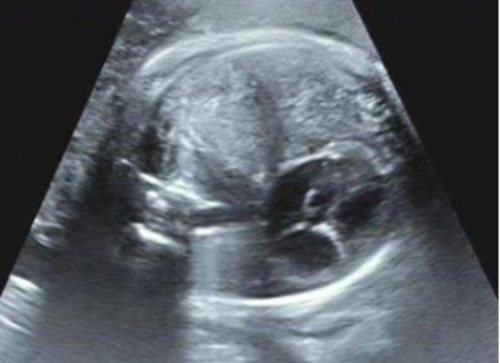

被告知檢查結果后,胡女士一家開始四處求醫(yī),經(jīng)多方打聽,他們來到青島婦女兒童醫(yī)院尋求解決辦法。胎兒醫(yī)學中心接診專家為胡女士完善排畸超聲相關檢查后,診斷胎兒患有先天性膈疝。

“人體內(nèi)胸腔、腹腔由一層叫做膈肌的肌肉分離開,由于胎兒的膈肌缺損,現(xiàn)在腸管通過膈肌的孔洞,’竄’入胸腔,把原本應該在左側胸腔的心臟擠到了右側胸腔......”聽著專家的解釋,胡女士夫妻倆的心一下子懸了起來?!昂⒆右呀?jīng)在肚子里8個月了,情況到底怎么樣?”

為綜合評估胎兒的情況,產(chǎn)科中心、胎兒醫(yī)學中心、超聲科、小兒外科、心臟中心及麻醉科專家進行多學科會診,專家評估后認為胎兒為晚發(fā)型膈疝,評估肺頭比LHR2.8,觀測/臍帶LHR>55%,出生后生存率接近100%。好消息令夫妻倆喜極而泣。